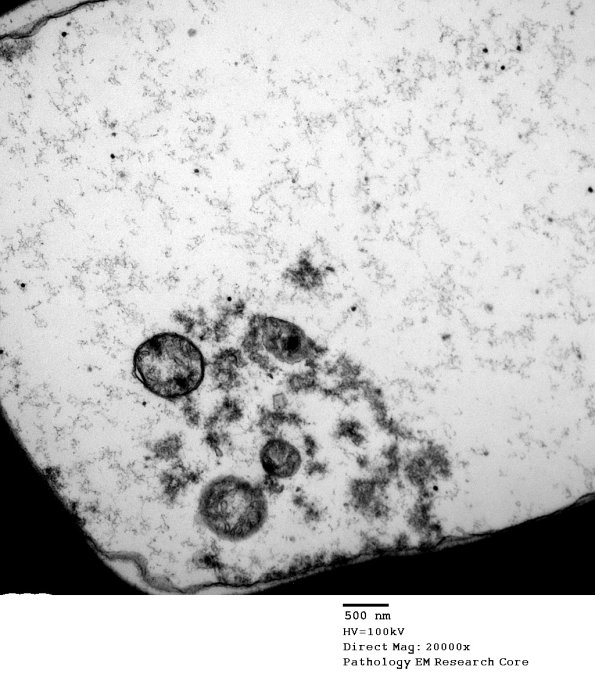

The loss of the cytoskeleton is accompanied by alterations in other axoplasmic organelles such as mitochondria, seen well at higher magnification in this image #1D2.